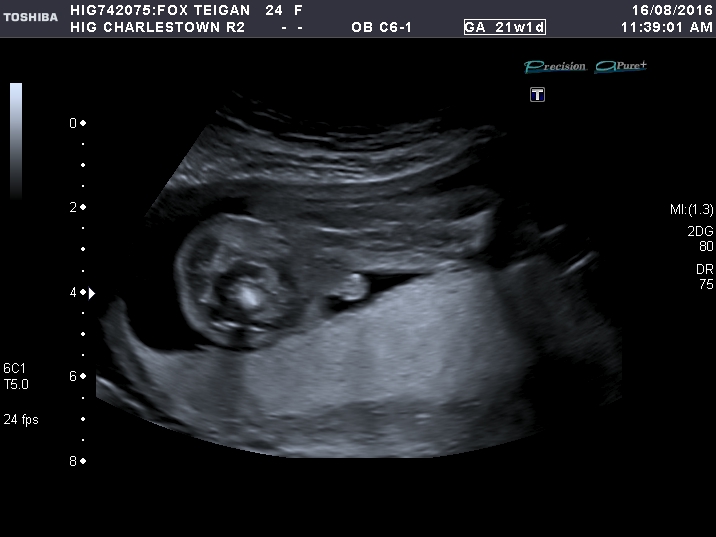

21 week scan :)

Sorry forgot to mention the more I look at the 21 weeks I think maybe its the cord? they had there legs shut for most of the scan to the very last try at a peak what's inbetween.